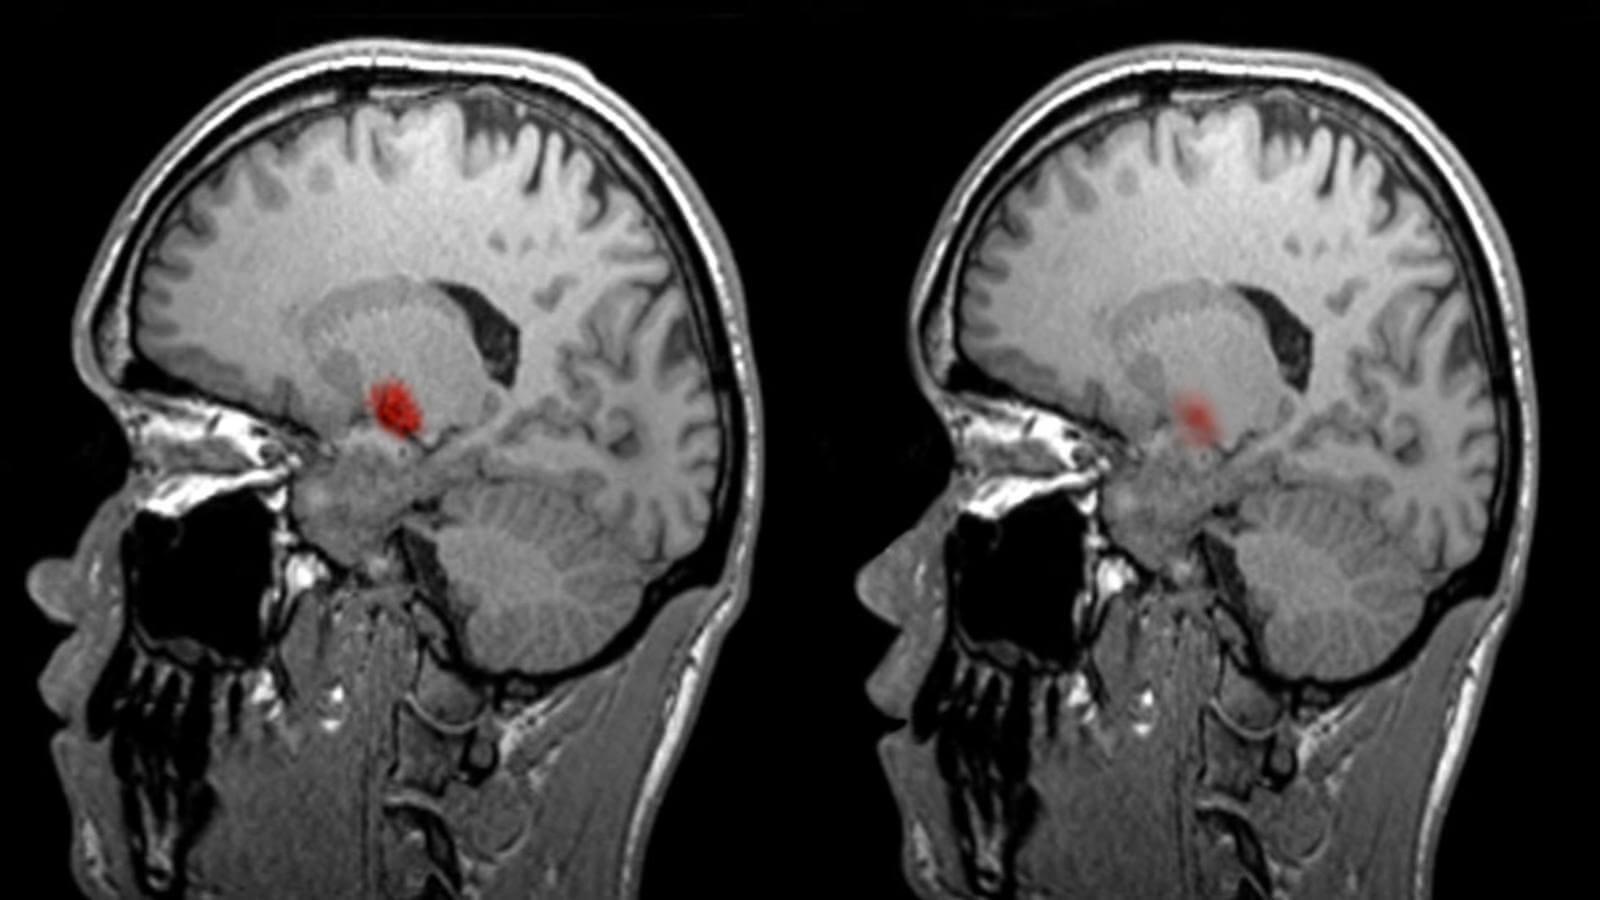

На что обратил бы внимание невролог вроде Джо Девлина, так это изменение кислорода в мозгу в действии. Если определенная часть мозга участвует в выполнении определенной задачи, скажем, языковой или словесной, эта область испытывает увеличение кровотока, который она использует ради энергии. Сканер фМРТ контролирует этот поток крови.

«Мы можем увидеть части мозга, которые загораются, когда вы выполняете эту задачу», — говорит Девлин. К примеру, если активно думать о том, что сказать, по сравнению с простым счетом — монотонной задачей, которая не требует особых умственных усилий, — становятся активными разные области мозга.

В то время как это дает понимание тех областей мозга, которые участвуют в актуальном деле, это даже близко не похоже на то, что фМРТ читает мысли человека.

И все же сканирование вроде этого уже произвело революцию в нашем понимании мозга. «Так сложилось, что у нас были пациенты с повреждениями мозга, и мы могли увидеть, где именно был поврежден мозг и что с пациентом не так», — говорит Девлин.

Однако сканирование позволяет ученым заглянуть и внутрь здорового мозга, чтобы отметить, как различные его части используются и соотносятся между собой.